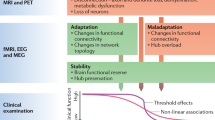

DTI allows the quantitative evaluation of WM microstructural integrity. Further, graph-theoretical approaches could be applied to the DTI-based connectivity matrix to explore the topological properties of the entire network. Changes in network metrics have been previously revealed in several psychological and neurological disorders such as MS and NMOSD7,8,9,10. Independent studies indicated decreases in global and local efficiencies in MS11 and in the total strength in NMOSD in comparison with healthy controls (HC)10. Disrupted WM networks also contributed to impaired cognition in MS and NMOSD patients8,10. However, few studies have compared the structural network changes in MS and NMOSD11,12. Indirect comparison was obtained, and which showed a greater number of disrupted brain regions in MS compared to NMOSD12. While patients with MS had less WM connections compared to HC, those with NMOSD only showed loss of small-word properties compared to HC11,12. They suggested that further studies are needed in the same cohort of MS and NMOSD using the same MRI scanner and analytical methods to investigate brain network differences12.

Disrupted brain network topology in MS and NMOSD

Overall, the MS and NMOSD groups had lower total strength, clustering coefficient, global efficiency, and local efficiency and had longer characteristic path length (CPL) than HC, but there were no differences between the MS and NMOSD groups (Table 2). Disease duration or Expanded Disability Status Scale (EDSS) score in the MS and NMOSD groups had positive correlation with CPL and negative correlation with the other global properties of network (Table 3). Since the longer CPL is coincident with the lower global efficiency, all showed the same trend. When compared with the HC group, brain regions with altered nodal characteristics were more widespread in the MS group than in the NMOSD group. The left medial orbital region of superior frontal gyrus had lower nodal degree and nodal strength and the left superior parietal gyrus, and precuneus had lower nodal strength in the MS and NMOSD groups compared with the HC group. The left fusiform gyrus and the right superior occipital gyrus in MS also had lower nodal strength compared with HC. Furthermore, significant differences were indicated among the nodal measures of several brain regions between the MS and NMOSD groups. The local efficiencies of the left hippocampus, left parahippocampal gyrus, left superior temporal gyrus, and right Heschl’s gyrus, and the regional efficiency of the left middle frontal gyrus were significantly lower in MS than in NMOSD. The brain regions with significant between-group differences within nodal measures are listed in Supplementary Table S2. The correlation results between nodal measures of the brain regions and clinical parameters were listed in Supplementary Table S3.

Disrupted global topological organization of WM networks was demonstrated in both MS and NMOSD, with no differences between these two conditions. However, at the nodal level, the MS group had more brain regions with altered metrics than did the NMOSD group when compared with the HC group. Furthermore, the left hippocampus, left parahippocampal gyrus, left superior temporal gyrus, and right Heschl’s gyrus of the MS group had greater decreases in local efficiencies compared with the NMOSD group. Two distinct subnetworks were identified to characterize the disease groups. Disconnected edges were more widespread in the MS group compared with the NMOSD group, and discriminative connectivity changes were mostly found in the thalamus and inferomedial temporal regions. Network alterations were associated with EDSS score and disease duration in both groups.

The whole-brain WM networks of MS and NMOSD were characterized by reduced total strength, global efficiency, and local efficiency compared with HC. These changes were also correlated with higher EDSS scores and longer disease durations in both disease groups, which is consistent with previous studies11,15. Similar patterns of change in structural connectivity have been reported in MS11,16,17 and NMOSD12,18. Our previous study reported that patients with NMOSD only had reduced total strength compared with HC, which was likely due to including fewer patients with cerebral lesions (14% vs 44% in this study)10.